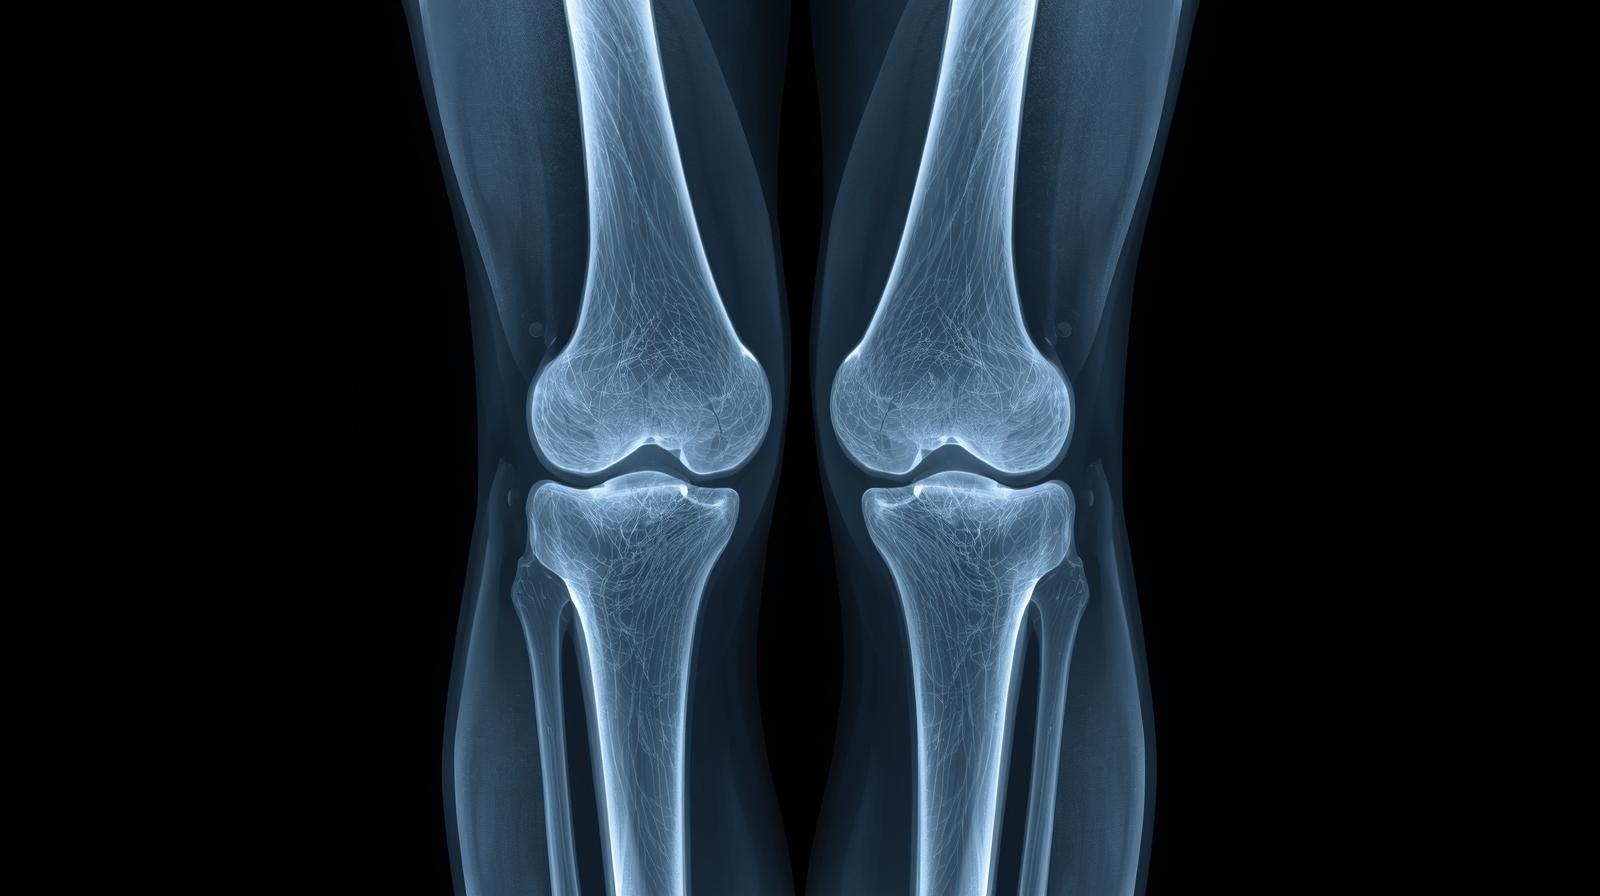

In a normal knee X-ray, the bones are properly aligned, the joint spaces are even, and there are no visible fractures or unusual bone growths. The X-ray can be taken from different angles to get a complete view of the joint. Common views include:

What a Normal Knee X-Ray Shows

A normal knee X-ray displays clear, well-defined bone structures without any signs of damage, deformity, or misalignment. Here’s what doctors look for in a normal image:

- Proper Joint Alignment: The femur, tibia, and patella are all in their correct positions.

- Normal Joint Space: The space between the bones should be even, indicating healthy cartilage.

- Smooth Bone Edges: The edges of the bones should be smooth without spurs or rough patches.

- No Fractures or Cracks: The bone surfaces should appear continuous without any breaks.

- Normal Bone Density: The bones should have consistent shading, showing healthy density and mineralization.

If the X-ray shows any narrowing of joint spaces, irregular bone surfaces, or abnormal shadows, it could indicate early signs of arthritis, cartilage wear, or other conditions.